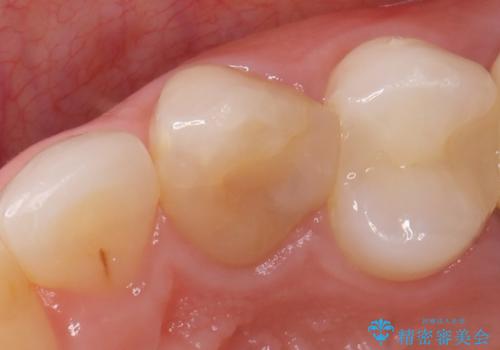

- 根管治療後歯が黄色くなってきたのでセラミックにしたいといらっしゃった方の症例です。

再根管治療後、オールセラミッククラウン(スペシャル)による補綴を行いました。

- オールセラミッククラウン(スペシャル)…¥130,000、仮歯…¥10,000、ファイバーコア…¥20,000費用は治療当時の料金となります